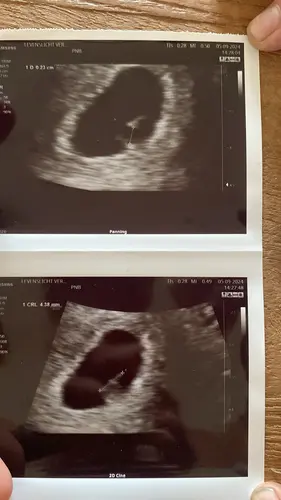

Vandaag met 5 weken en 2/3 dagen! We mochten een mooi kloppend hartje zien 😍😍💖

Vandaag met 5 weken en 2/3 dagen! We mochten een mooi kloppend hartje zien ...